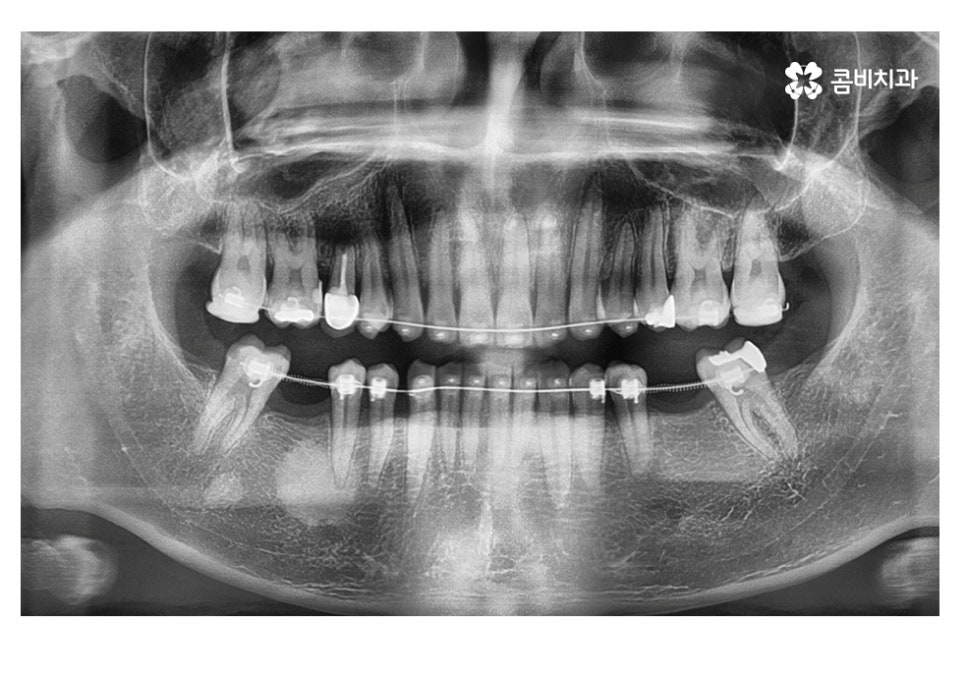

보통 임플란트와 교정을 같이 해야 하는 케이스에는

교정이 끝나기 약 6개월 전에 치료를 하게 되는 경우가 많은데

임플란트 식립 후 뼈가 완전히 굳고 치료를

마무리하기까지 보통 4~5개월 정도 걸리기 때문에

발치와 임플란트의 시술 그리고 교정이 비슷한 시기에

끝날 수 있도록 치료 계획을 세우고 있어요.